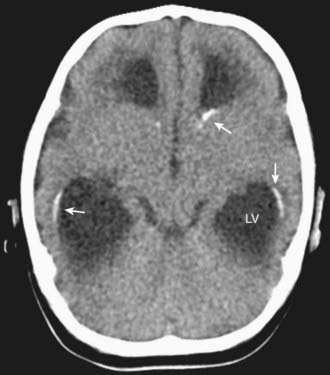

In congenital LCMV infection, laboratory findings in the newborn depend on whether active infection is still present. If the infant still harbors the infection, then examination of the CSF may reveal a lymphocytic pleocytosis. Unlike many other congenital infections, LCMV does not typically induce elevations in liver enzymes, thrombocytopenia, or anemia. In many cases, the most reliably abnormal findings are on the head CT scan, which typically reveals a combination of microencephaly, hydrocephalus, and periventricular calcifications (Fig. 264-1).

Figure 264-1 Head CT scan from a 2 mo old microcephalic baby with congenital lymphocytic choriomeningitis virus infection. The scan reveals enlargement of the lateral ventricles (LV) and periventricular calcifications (arrows).